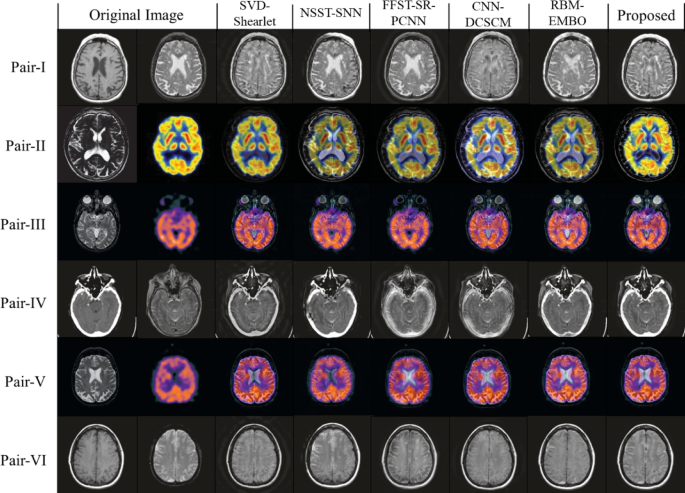

Applying 180 pairs of SI, the effectiveness of the proposed model is tested. The Harvard Medical School’s Whole Brain Atlas was used to compile the complete SI sample. A sample image set comprising CT, MRI, SPECT, and PET images was used in this study. Each SI’s gray and color scale spatial resolution is 512 × 512 pixels. The predictable 6 pairs of multimodal brain images, including CT, MRI, SPECT, and PET images, serve as a sample set for the experimental study results. The images in Pair I and Pair II are MR-T1 and MR-T2, MRI and PET are the images in Pair II, MR-T2, and SPECT are the images in Pair III, CT and MR-T2 are the images in Pair IV, MR-T2 is the image in Pair V, and MR-T1 and MR-T2 are the images in Pair VI.

Table 1 and Fig. 8 present the comparative performance of the proposed CNN + Shearlet fusion model against existing approaches. The proposed model proves superior performance across multiple evaluation metrics, particularly in preserving detailed features while maintaining overall image quality.

A graphical comparison in Fig. 8 reveals the precise advantages of the proposed model. Method 1 (SVD-Shearlet) displays blocking objects and fails to preserve detailed feature information, particularly in the highlighted regions. Method 2 (NSST + SNN) proves inadequate edge definition, particularly in Pairs I, III, IV, V, and VI, where acceptable anatomical boundaries appear blurred. Methods 3 (FFST + SR + PCNN) and Methods 4 (CNN + DCSCM) validate improved performance but still display insufficient edge clarity, as quantitatively confirmed by their lower QAB/F scores in Table 1. Method 5 (RBM + EMBO), despite presenting competitive performance in some metrics, generates images with low contrast in key regions, particularly noticeable in the upper proper portions of the IF.

In contrast, the proposed CNN + Shearlet model maintains optimal contrast levels, preserves fine structural details, and avoids introducing objects such as dark lines or blocking effects. The superior performance is particularly evident in the highlighted regions of Fig. 8, where the proposed method maintains clear tissue boundaries while preserving textural details in adjacent areas.

The comprehensive quantitative and qualitative analysis confirms that the proposed CNN + Shearlet fusion model outperforms existing methods across all evaluation metrics, significantly improving edge preservation (QAB/F) and feature detail retention (SF and IE).